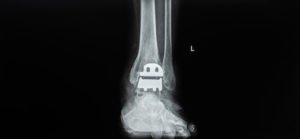

Contact your physician to discuss whether you need a revision surgery to replace your Exactech implant. Your doctor should order X-rays to help make an evaluation of your next steps.

The recalled Exactech Optetrak knee replacement system received “fast-track” 501(k) clearance from the FDA. It consists of patellar and femoral caps, a tibial insert, and a tibial tray.

TKR stands for total knee replacement surgery, and TAR stands for total ankle replacement surgery.